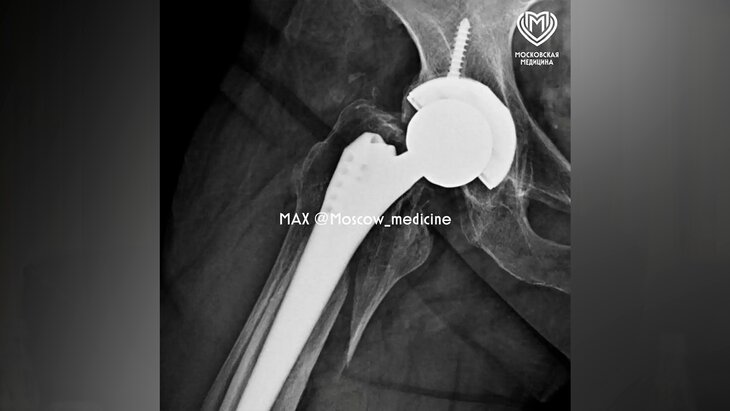

Фото: MAX/Московская медицина

Московские хирурги городской клинической больницы имени А. К. Ерамишанцева заново собрали пациентке бедренную кость. Операция заняла два часа, сообщила пресс-служба столичного Депздрава.

По данным ведомства, 66-летняя жительница Москвы торопилась на работу, однако упала и получила перелом бедренной кости. Травма была зафиксирована в том месте, где в 2018 году женщине установили эндопротез.

Во время операции хирурги удалили нестабильные фрагменты, собрали костные отломки с помощью серкляжной системы и установили новый эндопротез. Спустя шесть дней женщину выписали домой на реабилитацию.